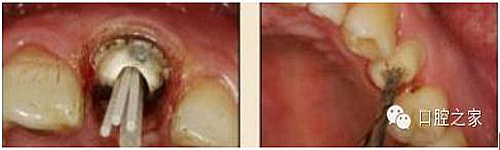

8.根管內(nèi)酸蝕劑的去除

使用全酸蝕粘結(jié)系統(tǒng)粘接纖維樁時,需要應(yīng)用磷酸凝膠對根管進(jìn)行酸蝕處理,然后再徹底沖洗干凈。根管內(nèi)酸蝕劑的殘留是臨床上經(jīng)常發(fā)生且容易被忽視的問題,也是影響纖維樁粘接的重要因素之一。單獨使用三用槍即使反復(fù)沖洗也很難將根管內(nèi)的酸蝕劑清除干凈,尤其是后牙根管。臨床建議應(yīng)用注射器、三用槍和柱狀毛刷,三者聯(lián)合使用反復(fù)沖洗,以免酸蝕劑殘留于根管內(nèi)(圖 19-1至圖 19-4)。有條件者也可使用超聲波蕩洗根管。

圖19-1:冠部及根管全酸蝕。圖19-2:三用槍沖洗。圖19-3:注射器沖洗。 圖19-4:根管毛刷清洗。